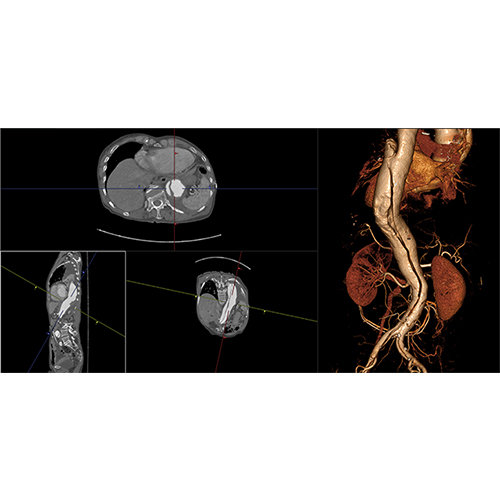

View X-Ray CT & MRI Scans Fast and Easily

High-quality and fast 3D reconstruction and 3D rendering

Performs 3D reconstruction and volume rendering.

Multi-planar slicing.

Oblique slicing.

Side-by-side comparative assessment for pre- and post-operative scans.